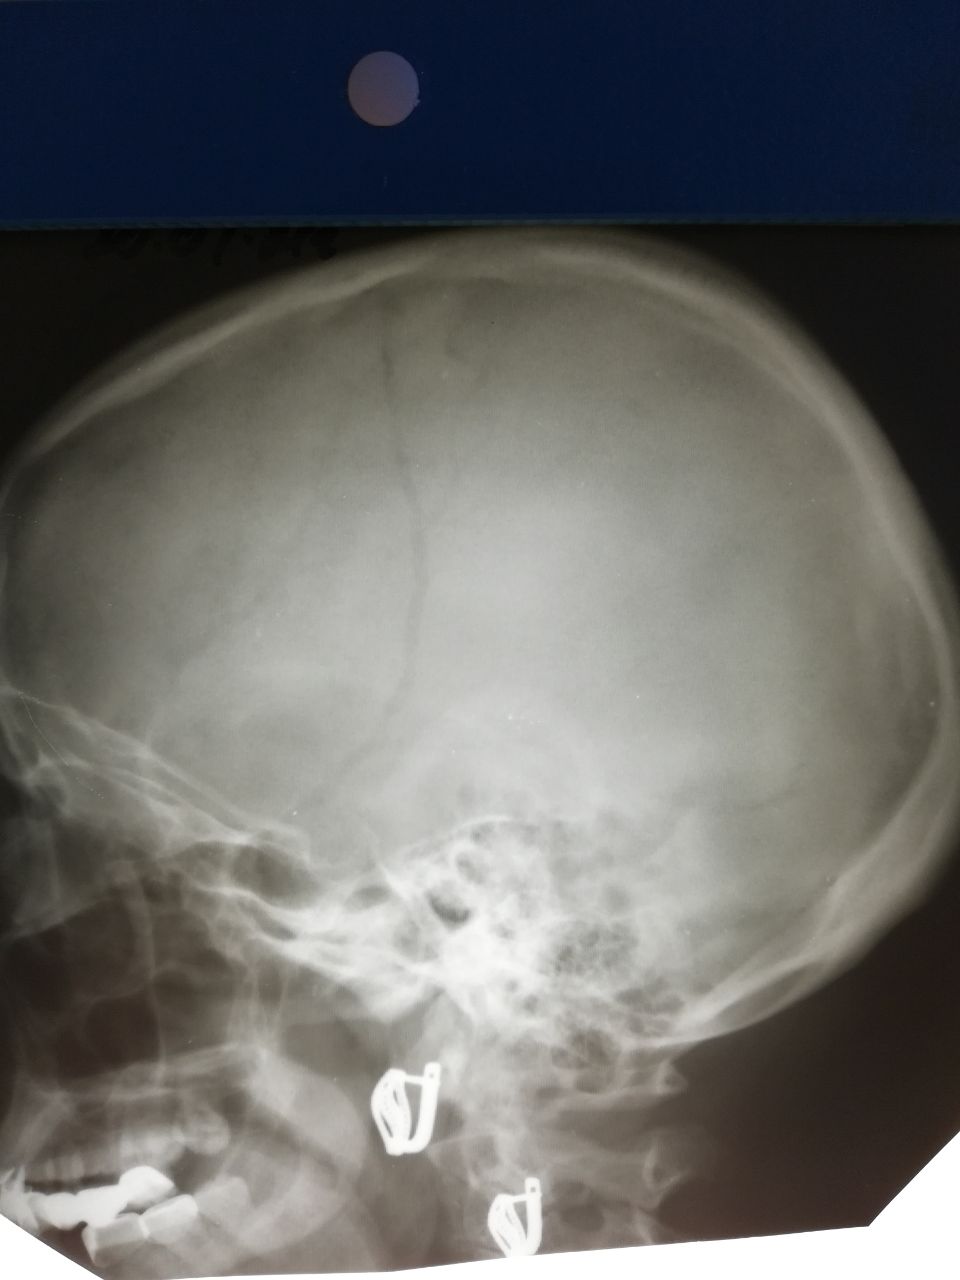

Нина Панаетова-Кумба... in Radiology/Рентгенология Чат

Добрый день, коллеги! Это же тень сосуда?

Сравните архивом и анамнезом

Архива нет. "Упала, ударилась лбом"

Это не перелом